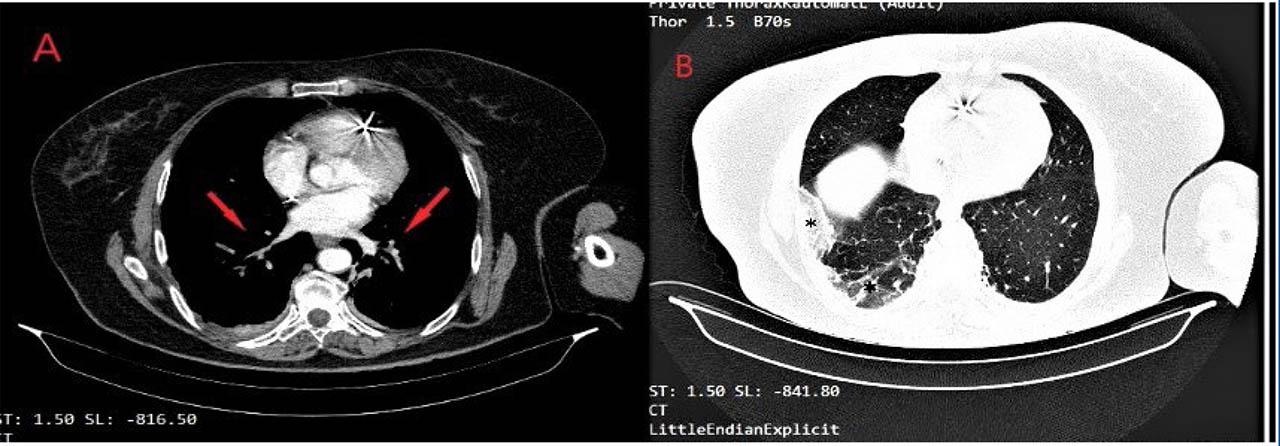

Figure 4

Contrast pulmonary CT scan. Panel A: multiple bilateral thrombi in segmental and subsegmental pulmonary arteries; Panel B: alveolar and interstitial densification areas localized in the lower inferior right lobe – probably pulmonary infarcts.